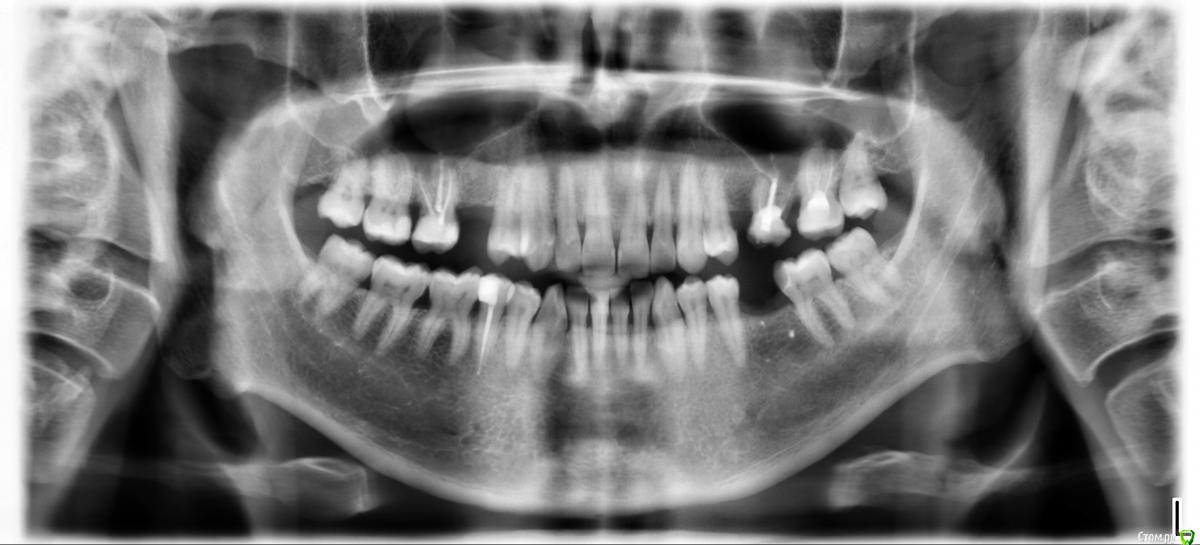

Ulitka Опубликовано 31 января, 2021 Поделиться Опубликовано 31 января, 2021 Добрый день.Ортопед предложил установить коронки на 16 и 27, а 26 удалить. Терапевт пока пролечила каналы в 16 и заложила лекарство на месяц, поставила временную пломбу. Сказала на 27 можно коронку пока не ставить. На консультацию к хирургу скоро пойду по поводу отсутствующих зубов.Действительно ли 26 нужно удалять и нельзя поставить коронку?На какие зубы нужно ставить коронки, на Ваш взгляд? Ссылка на комментарий

red_butler Опубликовано 31 января, 2021 Поделиться Опубликовано 31 января, 2021 на снимке действительно 2.6 выглядит плохо Ссылка на комментарий

red_butler Опубликовано 3 февраля, 2021 Поделиться Опубликовано 3 февраля, 2021 А на какие еще зубы нужно коронки поставить?1.6 2.7 4.5 Ссылка на комментарий